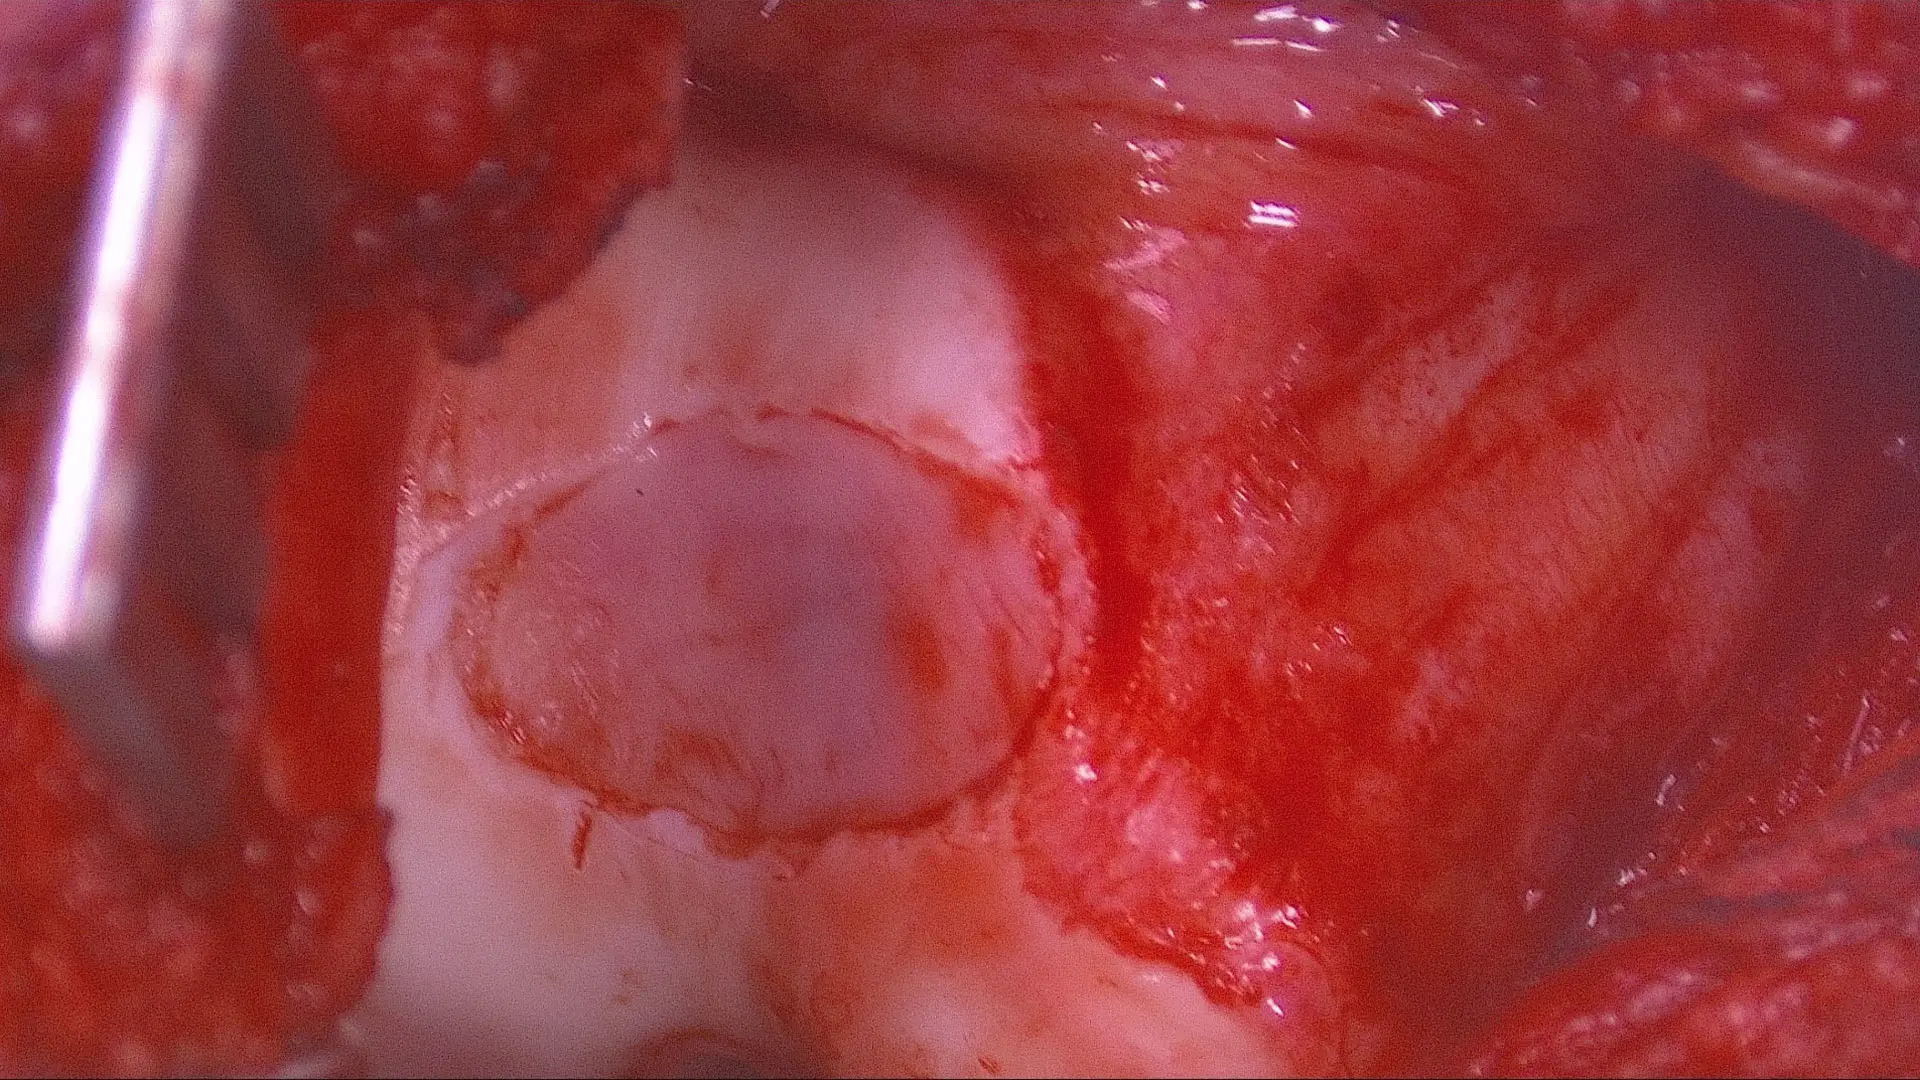

Appearance of torn ACL, good stump appropriate for BEAR procedure.

Cartilage damage on the end of the trochlea through which the kneecap (patella) glides when the knee bends and extends.

Preparation of the defect by removing all the damaged cartilage down to bone.

Area of cartilage damage marked out.